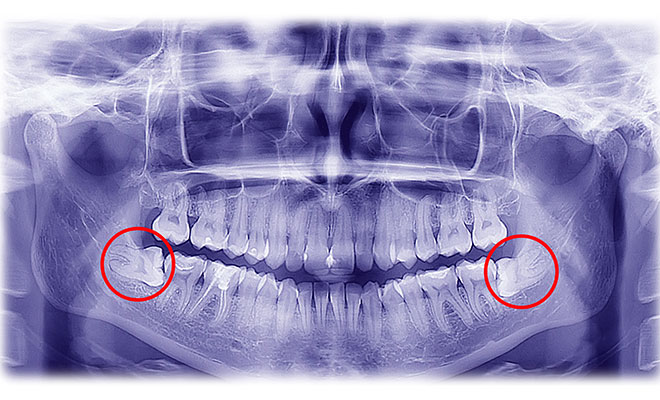

Impacted wisdom teeth

Wisdom teeth become impacted when there is no space for them to erupt into the mouth completely. They can either be impacted against the gums, against the jawbone, or against the adjacent teeth. They lie in a compromised position and are not useful for proper function. They can be difficult to clean, often leading to infection around the gums, or decay in the neighbouring teeth. They can also lead to formation of jaw cysts. Impacted wisdom teeth are also one of a number of factors in a crowded dentition and are often removed for example, after having orthodontic treatment.